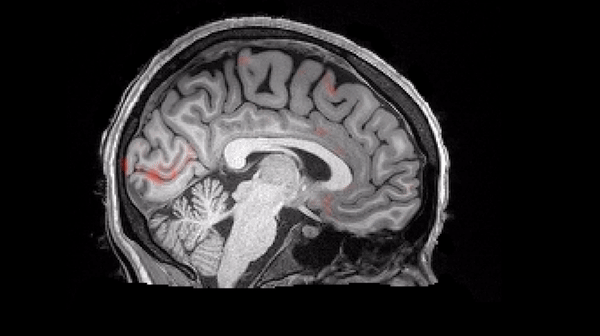

Elizabeth Michael and her colleagues wanted to investigate whether entraining peoples’ alpha waves could improve their performance on a visual discrimination task. To do so, they used EEG to record and determine the exact frequency of alpha waves in 80 study participants. They then used flickering visual stimuli to entrain the participants. The participants were shown a white square flickering against a dark background for 1.5 seconds, with the square flickering at a rate that matched each participant’s peak alpha frequency. When the flickering stimulus was exactly in phase with a participant’s individual frequency, the power of their alpha waves increased. This did not occur if the flickering was out of sync with the individual’s frequency.

After entrainment, the participants performed a visual discrimination task, in which they viewed “noisy” images and had to identify which of two different patterns each one contained. These images were set to be shown in time either at the peaks of each participant’s alpha wave oscillations or at the troughs. The participants were far better at identifying patterns in stimuli presented at the troughs of their alpha waves. This may be because the alpha wave troughs are associated with a disinhibition mechanism that improves visual target detection by regulating nerve cell excitability in the visual cortex.